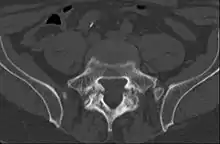

Computed tomography

Commonly known as a CT Scan or CAT scan, this form of imaging is very similar to x-ray technology but produces many more images than an x-ray does. The multiple images produce cross-sectional views not possible with an x-ray. This allows a physician or radiologist to examine the images from many more angles than an x-ray allows. For this reason the CT scan is much more accurate in detecting spondylolysis than an x-ray. Bone scintigraphy combined with CT scan is considered the gold standard which means that it is best at detecting spondylolysis.[12][14]